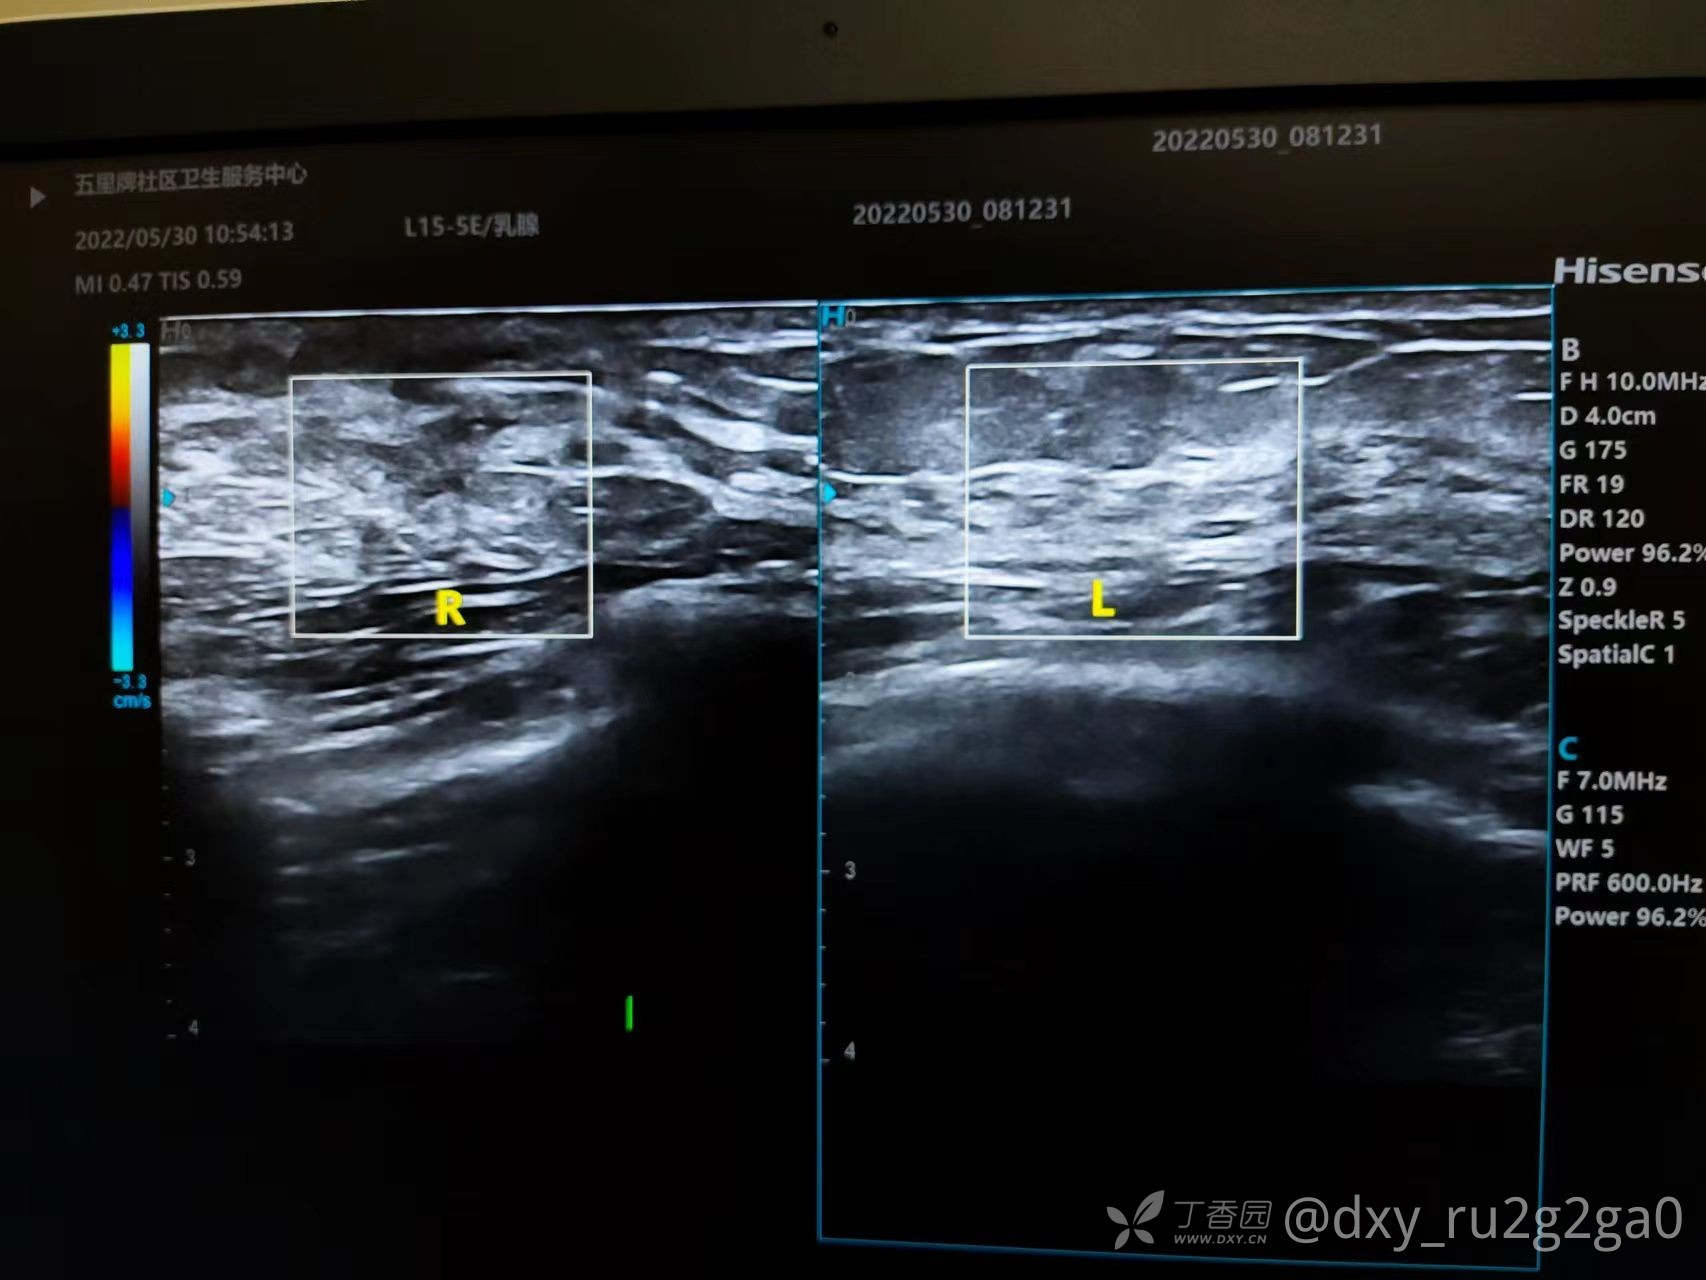

该病例21岁未婚 右胸偶感疼痛 如针刺样 触诊有肿块

img